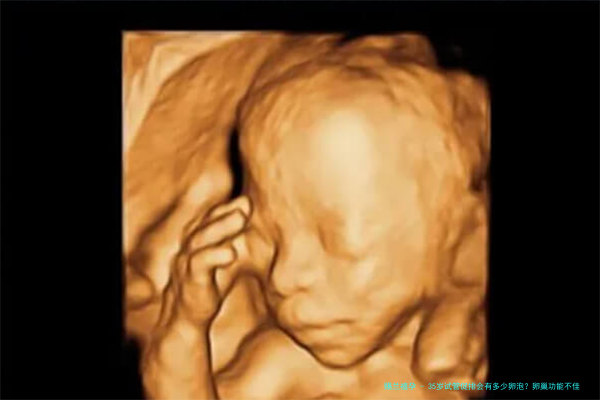

35岁女性进行试管婴儿(试管婴儿)促进排卵的时候,卵泡的数目会受到岁数、卵巢储存功能以及个别差别的影响。正常情况下,35岁的女性卵巢机能已然开始逐步降低,但仍旧身在相应较好的阶段。在促排期间,医生会根据病患的详尽情形拟订个体化的用方剂案,平常可以取得5-十五个成熟卵泡。固然,这一范畴因个体不同而不同,单方面女性可能会获更加多的卵泡,而卵巢功效较差的女性则可能数目较少。